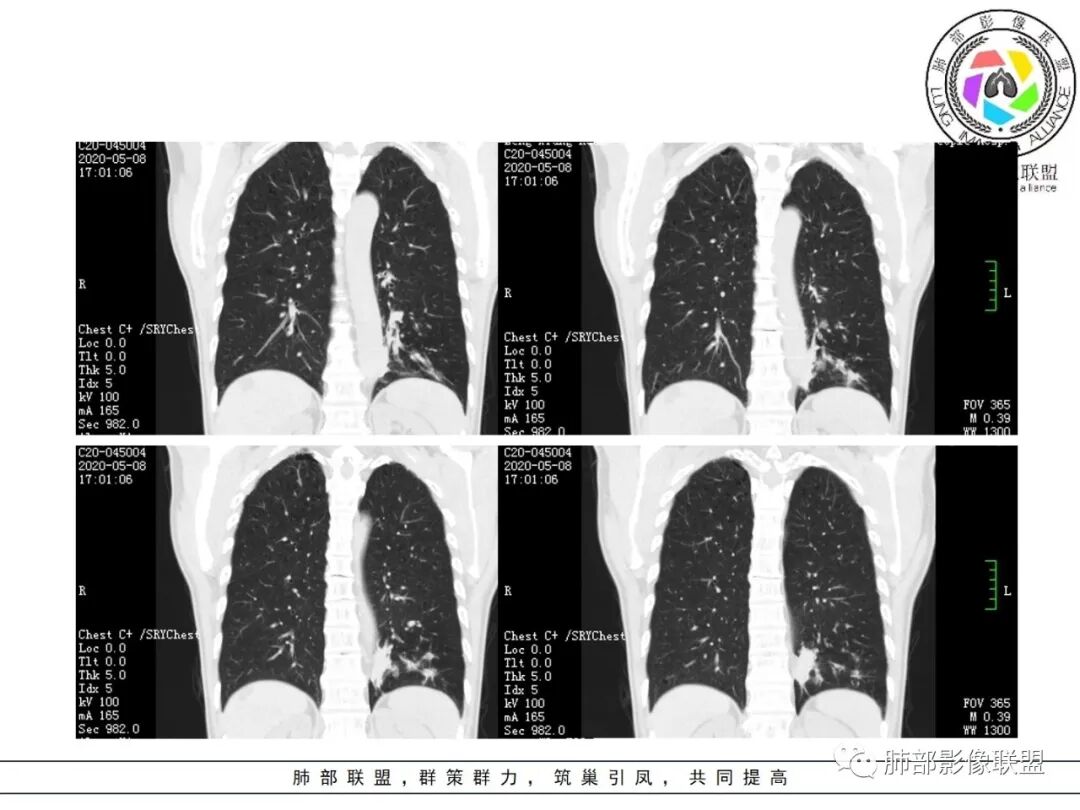

1.关于病灶分布:本例多发小片影局限在左肺下叶,其他肺叶未见异常病灶。

而肺结核表现为多灶性、多形态、多钙化性,本例前述征象均未见到,亦未见结核的典型树芽征。故肺结核缺乏支持点。

2.关于支气管:上述病灶辖区外侧段支气管截断,环壁结节,远端阻塞性肺炎,是肺癌的重要征象。